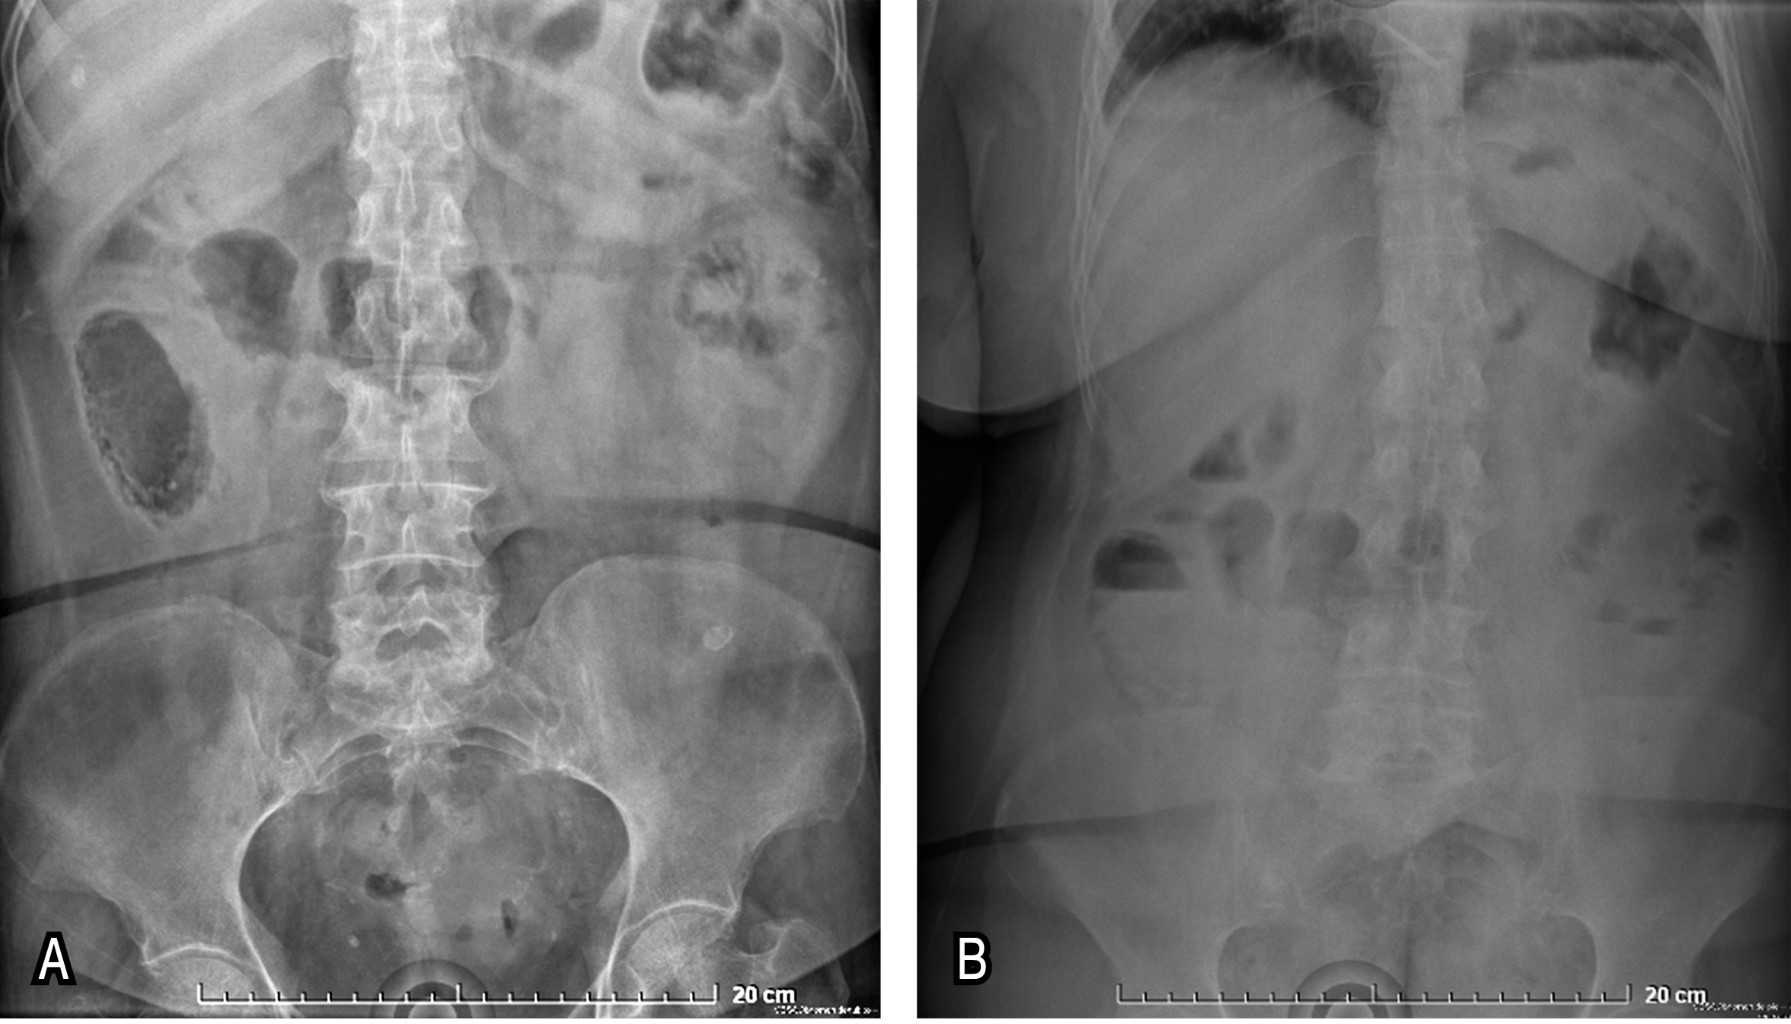

Abdominal plain X-rays (recumbent and standing) showed a sentinel loop and a hydro-aerial level in the right lower quadrant (RLC) (Figure 1). A clinical diagnosis (Alvarado score of 8) of appendicitis was made and an appendectomy by exploratory laparotomy was scheduled. An infraumbilical median incision was made, and upon reaching the cavity, intestinal inflammation of the distal ileal region, cecum and ascending colon was corroborated. When the cecum was lifted, a full-thickness necrosis of partial extension (6 × 8 cm) was found at the level of the antimesenteric border. This necrosis had well delimited borders, while the rest of the cecum and appendix were adequately perfused, with no macroscopic data of ischemic distress. There were no other important findings (Figure 2). The distal ileum segment (5 cm) and the entire cecum were resected, closing the ascending colon in a Hartmann's pouch (in two planes, with 2-0 polyglactin 910 suture), leaving a terminal ileostomy.

Figure 1